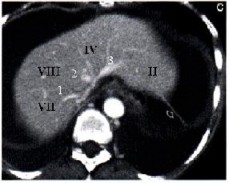

1.1.4. Phân chìa thùy và phân thùy gan trên CLVT:

Sự phân chia thuỳ và hạ phân thuỳ gan trên CLVT cũng dựa trên các mốc mạch máu đó là các tĩnh mạch gan và các nhánh phải và trái của tĩnh mạch cửa, các mặt phẳng tưởng tượng đi qua các mạch máu trên giúp phân biệt vị trí các thuỳ và phân thuỳ gan. Mặt phẳng qua TM gan phải chia gan phải thành phân thuỳ trước và sau. Mặt phẳng qua TM gan giữa chia gan thành gan phải và trái. Mặt phẳng qua TM gan trái chia gan trái thành thuỳ vuông và thuỳ đuôi. Mặt

phẳng ngang đi qua nhánh phải và trái phân chia các HPT trên gồm II, IVa, VII, VIII với các HPT dưới gồm III, IVb, V, VI [11].

Hình 1.3: Lớp cắt cao phía trên thấy r 3 tĩnh mạch gan (1 TM gan phải, 2 TM gan giữa, 3 TM gan trái) cho phép xác định các HPT II, IV, VIII, VII [11].